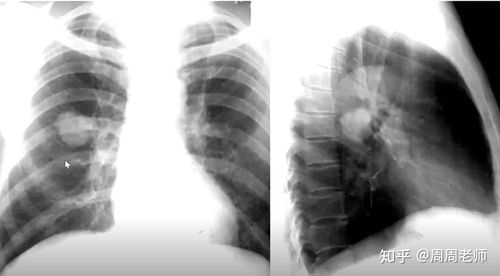

肺不张胸片典型图片

肺不张胸片典型图片,肺不张胸片表现图片

肺不张胸片表现图片

肺不张胸片表现

肺不张胸片

肺不张x线表现

肺不张x线